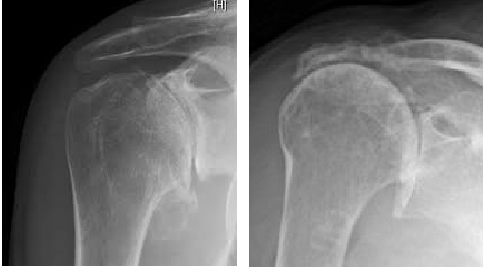

Figure 1 Two patterns of shoulder arthritis. Osteoarthritis on the left, Rotator Cuff Arthropathy on the right (note the humeral head is not centred in the socket in the right hand image)